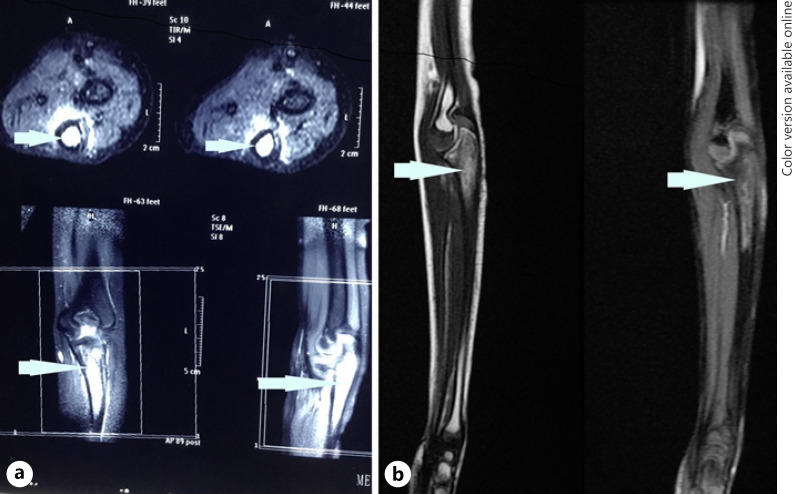

Six and a half years after treatment, the child presented with pain in his left proximal forearm. On examination, there was mild tenderness over the proximal ulnar bone, with no obvious swelling or redness. Radiograph showed lytic sclerotic lesion involving proximal meta-diaphysis of the left ulna with wide zone of transition, solid periosteal reaction, and cortical irregularities (shown in Fig. 1). MRI further confirmed the lesion limited to proximal meta-diaphysis of the left ulna seen as abnormal STIR hyperintensity involving the marrow with cortical erosion and associated soft tissue component (shown in Fig. 2). The bone scan showed uptake only at the left upper forearm. Bone marrow and CSF analysis did not show any evidence of disease. The CT thorax did not show any pulmonary metastasis. Bone biopsy was done, and histopathology showed infiltration of the intertrabecular space by sheets of small round cells having scanty cytoplasm and hyperchromatic nuclei. The differentials considered were small cell osteosarcoma, Ewing's sarcoma, and metastatic small round cell neoplasm. Radiology was not suggestive of osteogenic sarcoma; hence, small-cell osteosarcoma was ruled out. Immunohistochemistry showed tumour cells to be chromogranin cytoplasmic granular positive, synaptophysin diffuse strong positive, CD56 diffuse strong positive, MIC2 cytoplasmic and membrane positive, desmin and myogenin negative (shown in Fig. 3). The tumour cells were positive for synaptophysin, chromogranin, and CD 56, which denotes neuroendocrine/neuroectodermal differentiation. Retinal markers were not done due to non-availability. Ewing's sarcoma translocations done were negative for EWS-FLI1 type 1 and type 2 and EWS-ERG, which together account for 95% of translocations associated with Ewing's sarcoma. Tumour cells in Ewing's sarcoma can be CD56 and synaptophysin positive, but chromogranin negative. Positivity for chromogranin, absence of typical crisp membrane pattern of staining for CD99, and negative translocation ruled out Ewing's sarcoma. Hence, we considered metastatic small round-cell neoplasm in this case. Based on the immunoprofile which showed positive staining for chromogranin, synaptophysin, and CD56, negative RT-PCR for translocations of Ewing's sarcoma, and a positive history of bilateral RB, the possibility of metastatic RB was highly favoured [13].

Fig. 2.

aPre-chemo T2W/STIR MRI: hyperintense marrow signal in proximal meta-diaphysis, cortical erosion, and minimal soft tissue component. b Post-chemo: residual marrow signal, hypointense in T1W/T2W, mild cortical thickening, and regression of soft tissue component.

The child was started on chemotherapy with vincristine 2 mg/m2 × 1 day, doxorubicin 30 mg/m2 × 1 day, cyclophosphamide 600 gm/m2 × 2 days alternating with cisplatin 100 mg/m2 × 1 day, and etoposide 100 mg/m2 × 5 days every 3 weeks. The child tolerated chemotherapy well with no major complications. After 7 cycles of chemotherapy, the child was re-evaluated. Both eyes showed no active tumour. Repeat X-ray was normal (Fig. 1), and MRI of the left forearm showed residual altered marrow signal intensity involving the proximal meta-diaphyseal region of the left ulna. There was near total regression of the extra-osseous soft tissue when compared to the previous scan (shown in Fig. 2). The child then underwent limb salvage surgery with wide local excision of the ulna at the metastatic site, followed by extracorporeal radiation and reimplantation therapy (ECRT). The bone segment bearing the tumour was resected, the tumour shaved off the bone, and the periosteum stripped. The resected bone segment was covered in an antibiotic soaked gauze, sealed in a sterile plastic, and transported to the radiation unit in a sterile manner where a single fraction of 50 Gy of radiation therapy was given extracorporeally using a 4 MV Elekta Synergy® S linear accelerator. The whole process takes a short time, while the patient continues to be under anaesthesia. The irradiated bone segment was then reimplanted as an auto graft and fixed to the remaining ulna with a 15-hole recon plate. The elbow capsule, the medial and the lateral ligaments were then reattached. Triceps tendon was also reattached. The post-operative period was uneventful. The histopathology of bone scrapings sent from the surgical margins did not show any viable tumour. After the surgery, the child received one more course of chemotherapy with vincristine, doxorubicin, and cyclophosphamide. The patient is now 1 year 11 months from the diagnosis of the ulnar lesion and remains recurrence-free. Repeat X-ray showed completely reunited bone. The child has a good range of movements and normal elbow function.